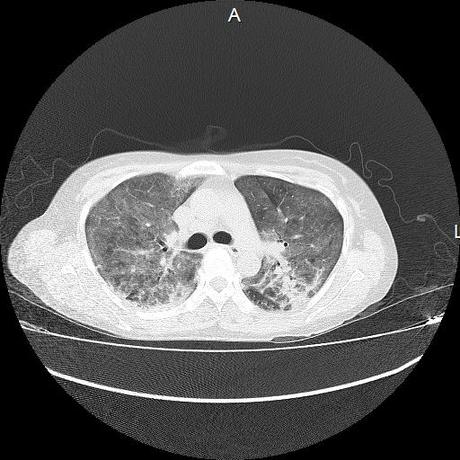

El parénquima pulmonar con areas parcheadas difusas en vidrio despulido combinadas con otras areas hipodensas de baja atenuación debidas a atrapamiento aéreo y engrosamiento intersticial y zonas de fibrosis de predominio en lóbulos medios e inferiores de ambos pulmones.

- LOS HALLAZGOS PUEDEN ESTAR EN RELACIÓN A NEUMOPATIA INTERSTICIAL PROBABLE ETIOLOGIA HIPERSENSITIVA VS AUTOINMUNE/BACTERIANA/FUNGICA.